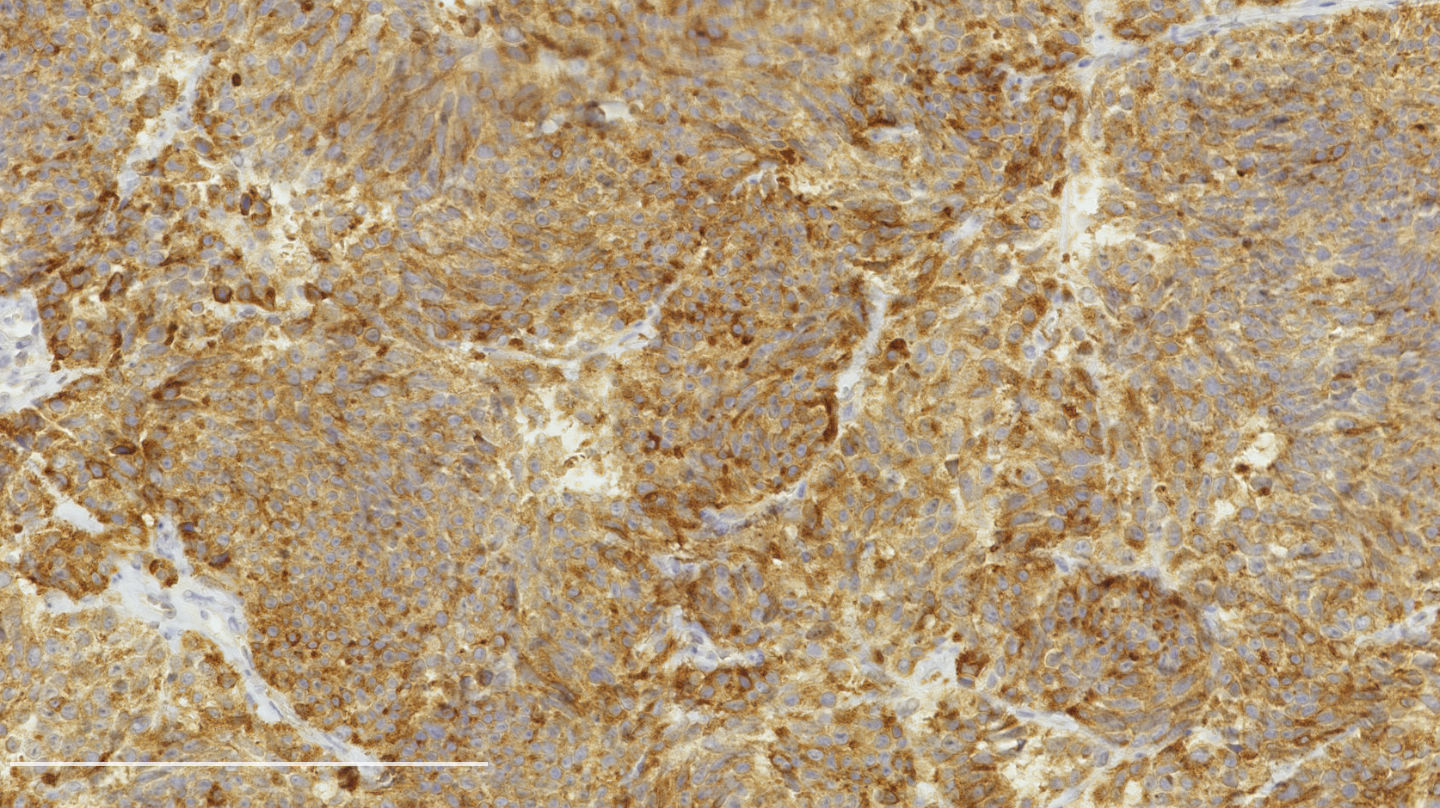

Contributed by Philippe Joubert, M.D., Ph.D.

Positive stains

- Chromogranin, synaptophysin, CD56: diffusely and strongly positive; can be negative in a small number of atypical carcinoids (Hum Pathol 2000;31:1255)

- Ki67: should not be used as a diagnostic criterion (J Thorac Oncol 2019;14:377)

- Mostly useful to differentiate lung carcinoids from high grade neuroendocrine carcinomas, in particular in small biopsies or cytology samples (Arch Pathol Lab Med 2018;142:947, J Thorac Oncol 2014;9:273)

- Usually < 20% but a > 30% cutoff has been proposed (Virchows Arch 2017;470:153, J Thorac Oncol 2014;9:273)

- Reported to be higher than typical carcinoid (2 - 5% versus 9 - 18%) but not proven to be a reliable marker